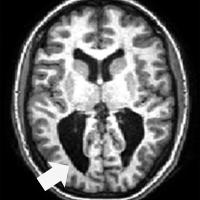

Cross-section of fMRI brain scan with arrow pointing to dark area

Vision loss in children whose eyesight may be 20/20 requires new diagnostic and teaching strategies

Cerebral (cortical) visual impairment (CVI) is a condition that interferes with the ability of the brain to process information from the eyes, and it has become a leading cause of visual impairment in the U.S.